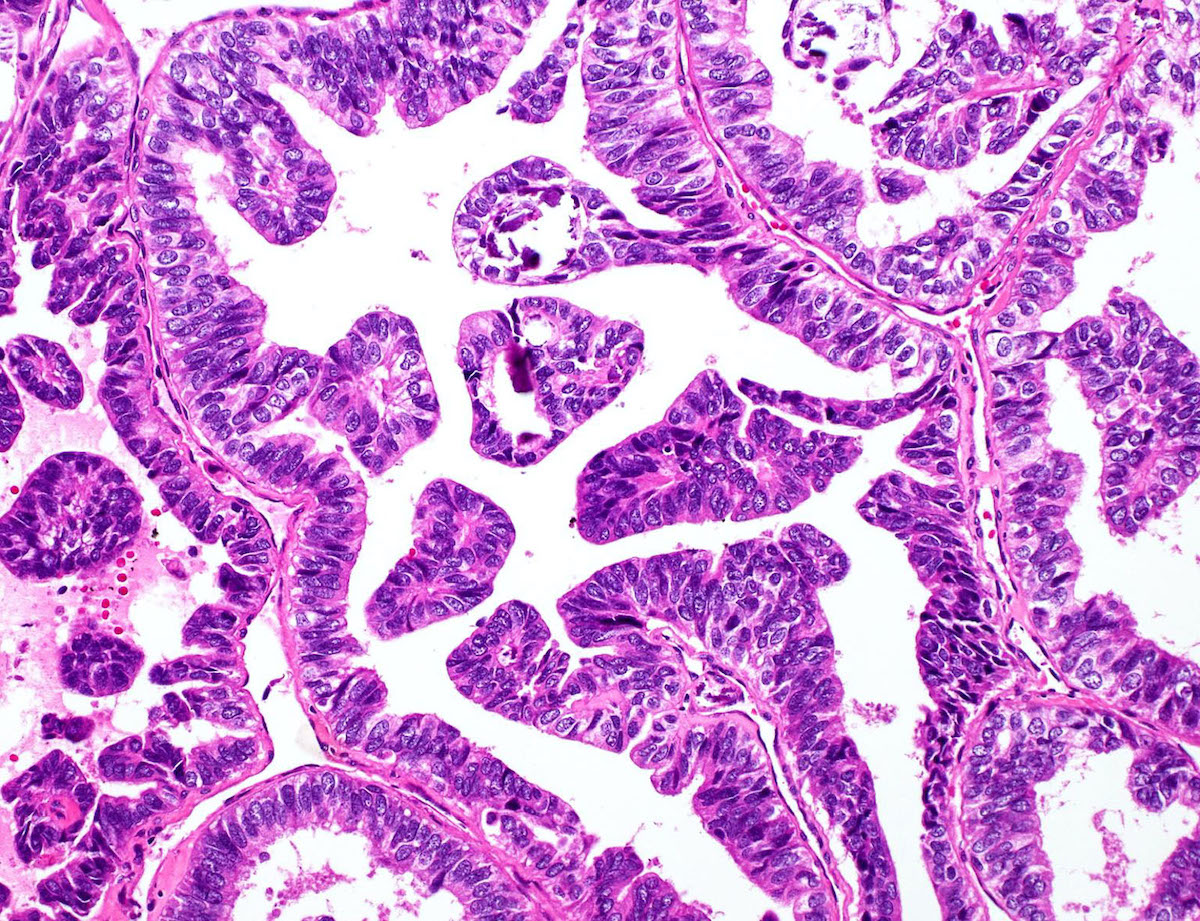

Is Columnar Cell Change Cancer . The world health organization currently classifies ccls without atypia as columnar cell change (ccc) and columnar cell hyperplasia. Columnar cell lesions in the breast have been recognised by histopathologists for a long period of time, but under a wide variety of names. With the increasing use of mammography screening scans in the last 30 years, columnar cell lesions (ccls) have been diagnosed. Flat epithelial atypia (fea) is a benign proliferative breast lesion characterized by columnar cell changes with cytologic atypia. Lacks low grade cytologic atypia of flat epithelial. Terminal duct lobular units are lined by columnar epithelial cells.

Terminal duct lobular units are lined by columnar epithelial cells. Flat epithelial atypia (fea) is a benign proliferative breast lesion characterized by columnar cell changes with cytologic atypia. Columnar cell lesions in the breast have been recognised by histopathologists for a long period of time, but under a wide variety of names. The world health organization currently classifies ccls without atypia as columnar cell change (ccc) and columnar cell hyperplasia. Lacks low grade cytologic atypia of flat epithelial. With the increasing use of mammography screening scans in the last 30 years, columnar cell lesions (ccls) have been diagnosed.